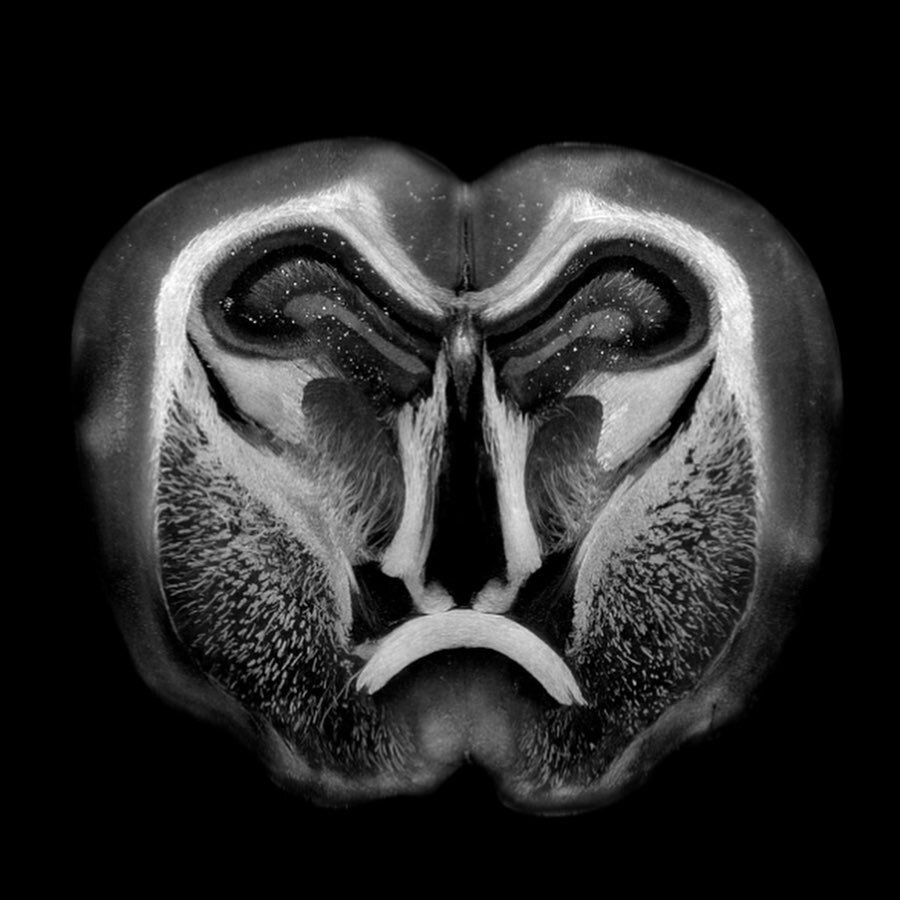

Синхротронный мозг мыши

Это жутковатое изображение и еще одно внизу — не шаманская маска и не портрет злобного бабуина. Это изображение секции мышиного мозга, которое получено методом рентгеновского фазового контраста с использованием рентгеновского синхротронного излучения одного из самых мощных в мире синхротронов с энергией в 6 ГэВ: European Synchrotron Radiation Facility (ESRF) в Гренобле. В этом синхротроне рентгеновское излучение получается за счет движения релятивистских (близких ко скорости света) электронов по искривленным магнитным полем траекторям. ESRF используют множество групп — от тех, кто занимается рентгеновской кристаллографией белков до тех, кто делает вот такие картинки или занимается палеонтологией или науками о материалах.

Ускоритель ESRF в Гренобле

Credit: European Synchrotron Radiation Facility — ESRF